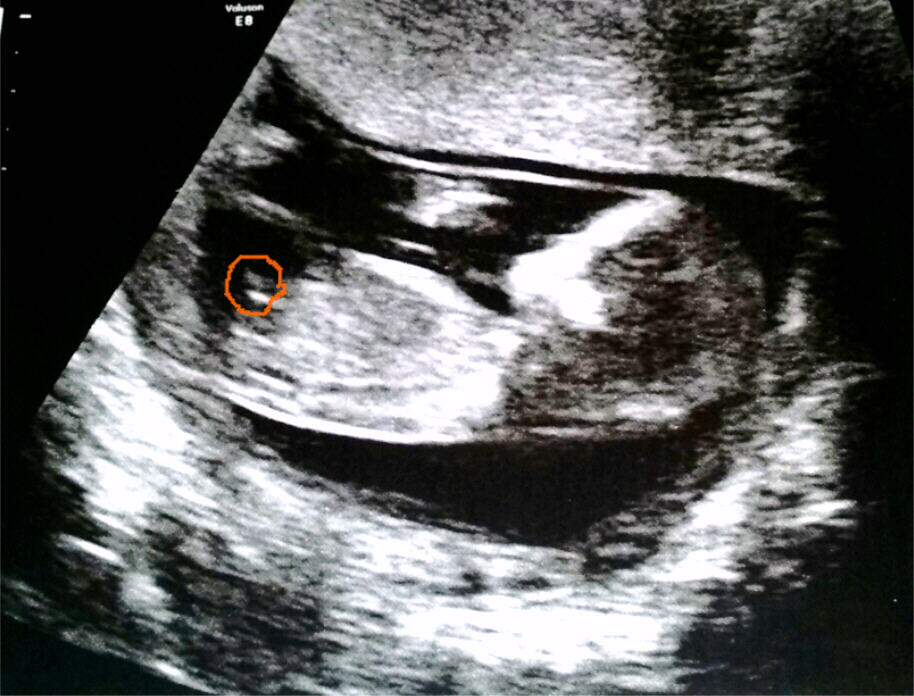

Just back from my 12 week scan and would love if ye could take a guess. My sonographer wasn't all too pleasant to deal with so couldn't get any guesses from her.

I am not sure that I'm seeing a nub, but if I am, I lean slightly boy bc it looks like there is some stacking already.

I brightened the pic on my desktop comp and I'm definitely thinking blue. I circled what I think is the nub for you.